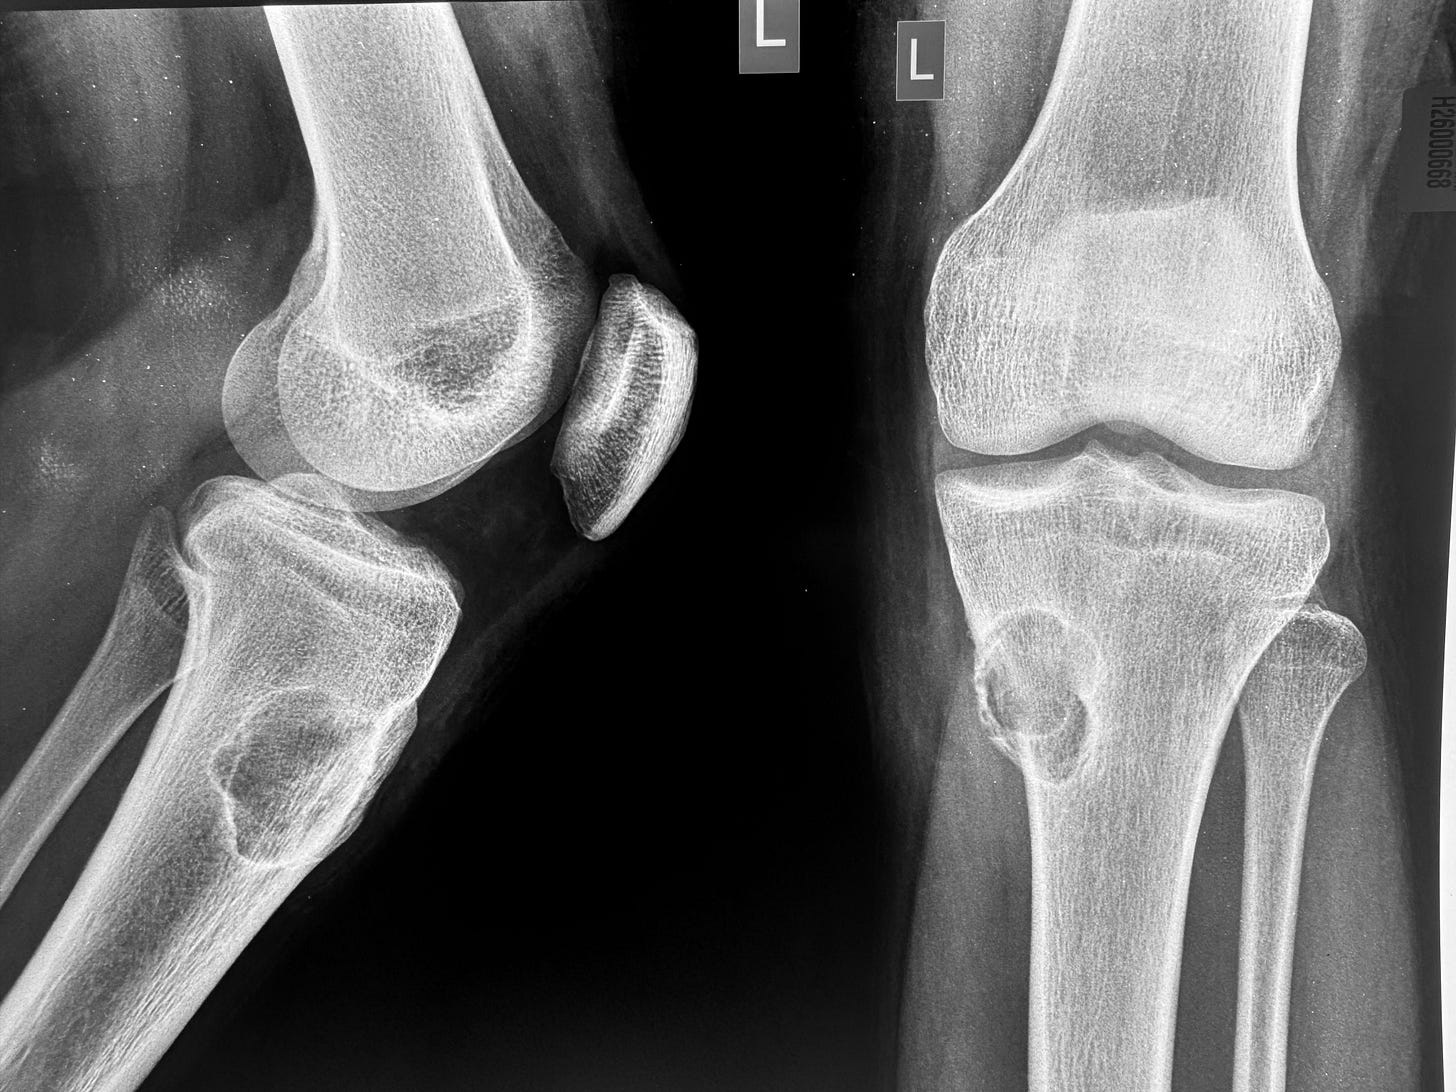

25-years old with knee pain.

X-ray shows an osteolytic lesion with a sclerotic rim - this is a benign lesion.